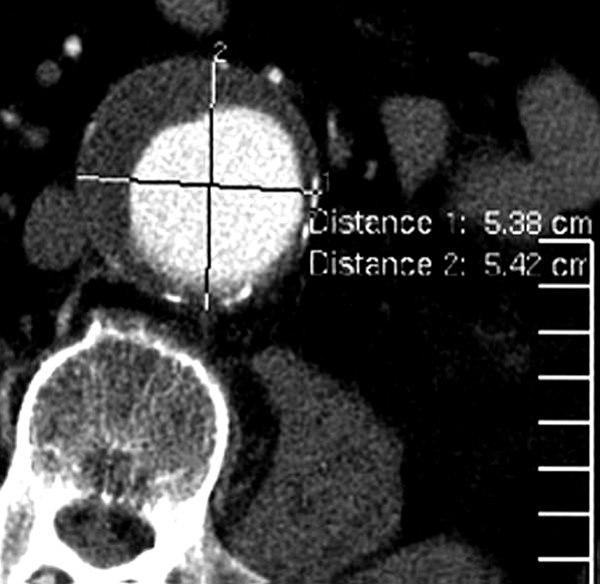

CT axialbilde med i.v. kontrast

Fusiformt aneurisme i bukaorta

Kontrastfylt lumen sentralt (lyst)

Trombemasser ut mot aortaveggen (mørkt)